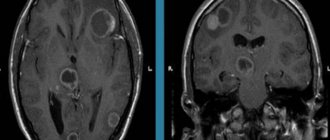

Токсоплазмоз на МРТ головного мозга

Токсоплазмоз на МРТ головного мозга Магнитно-резонансная томография является безболезненным и информативным способом исследования головного